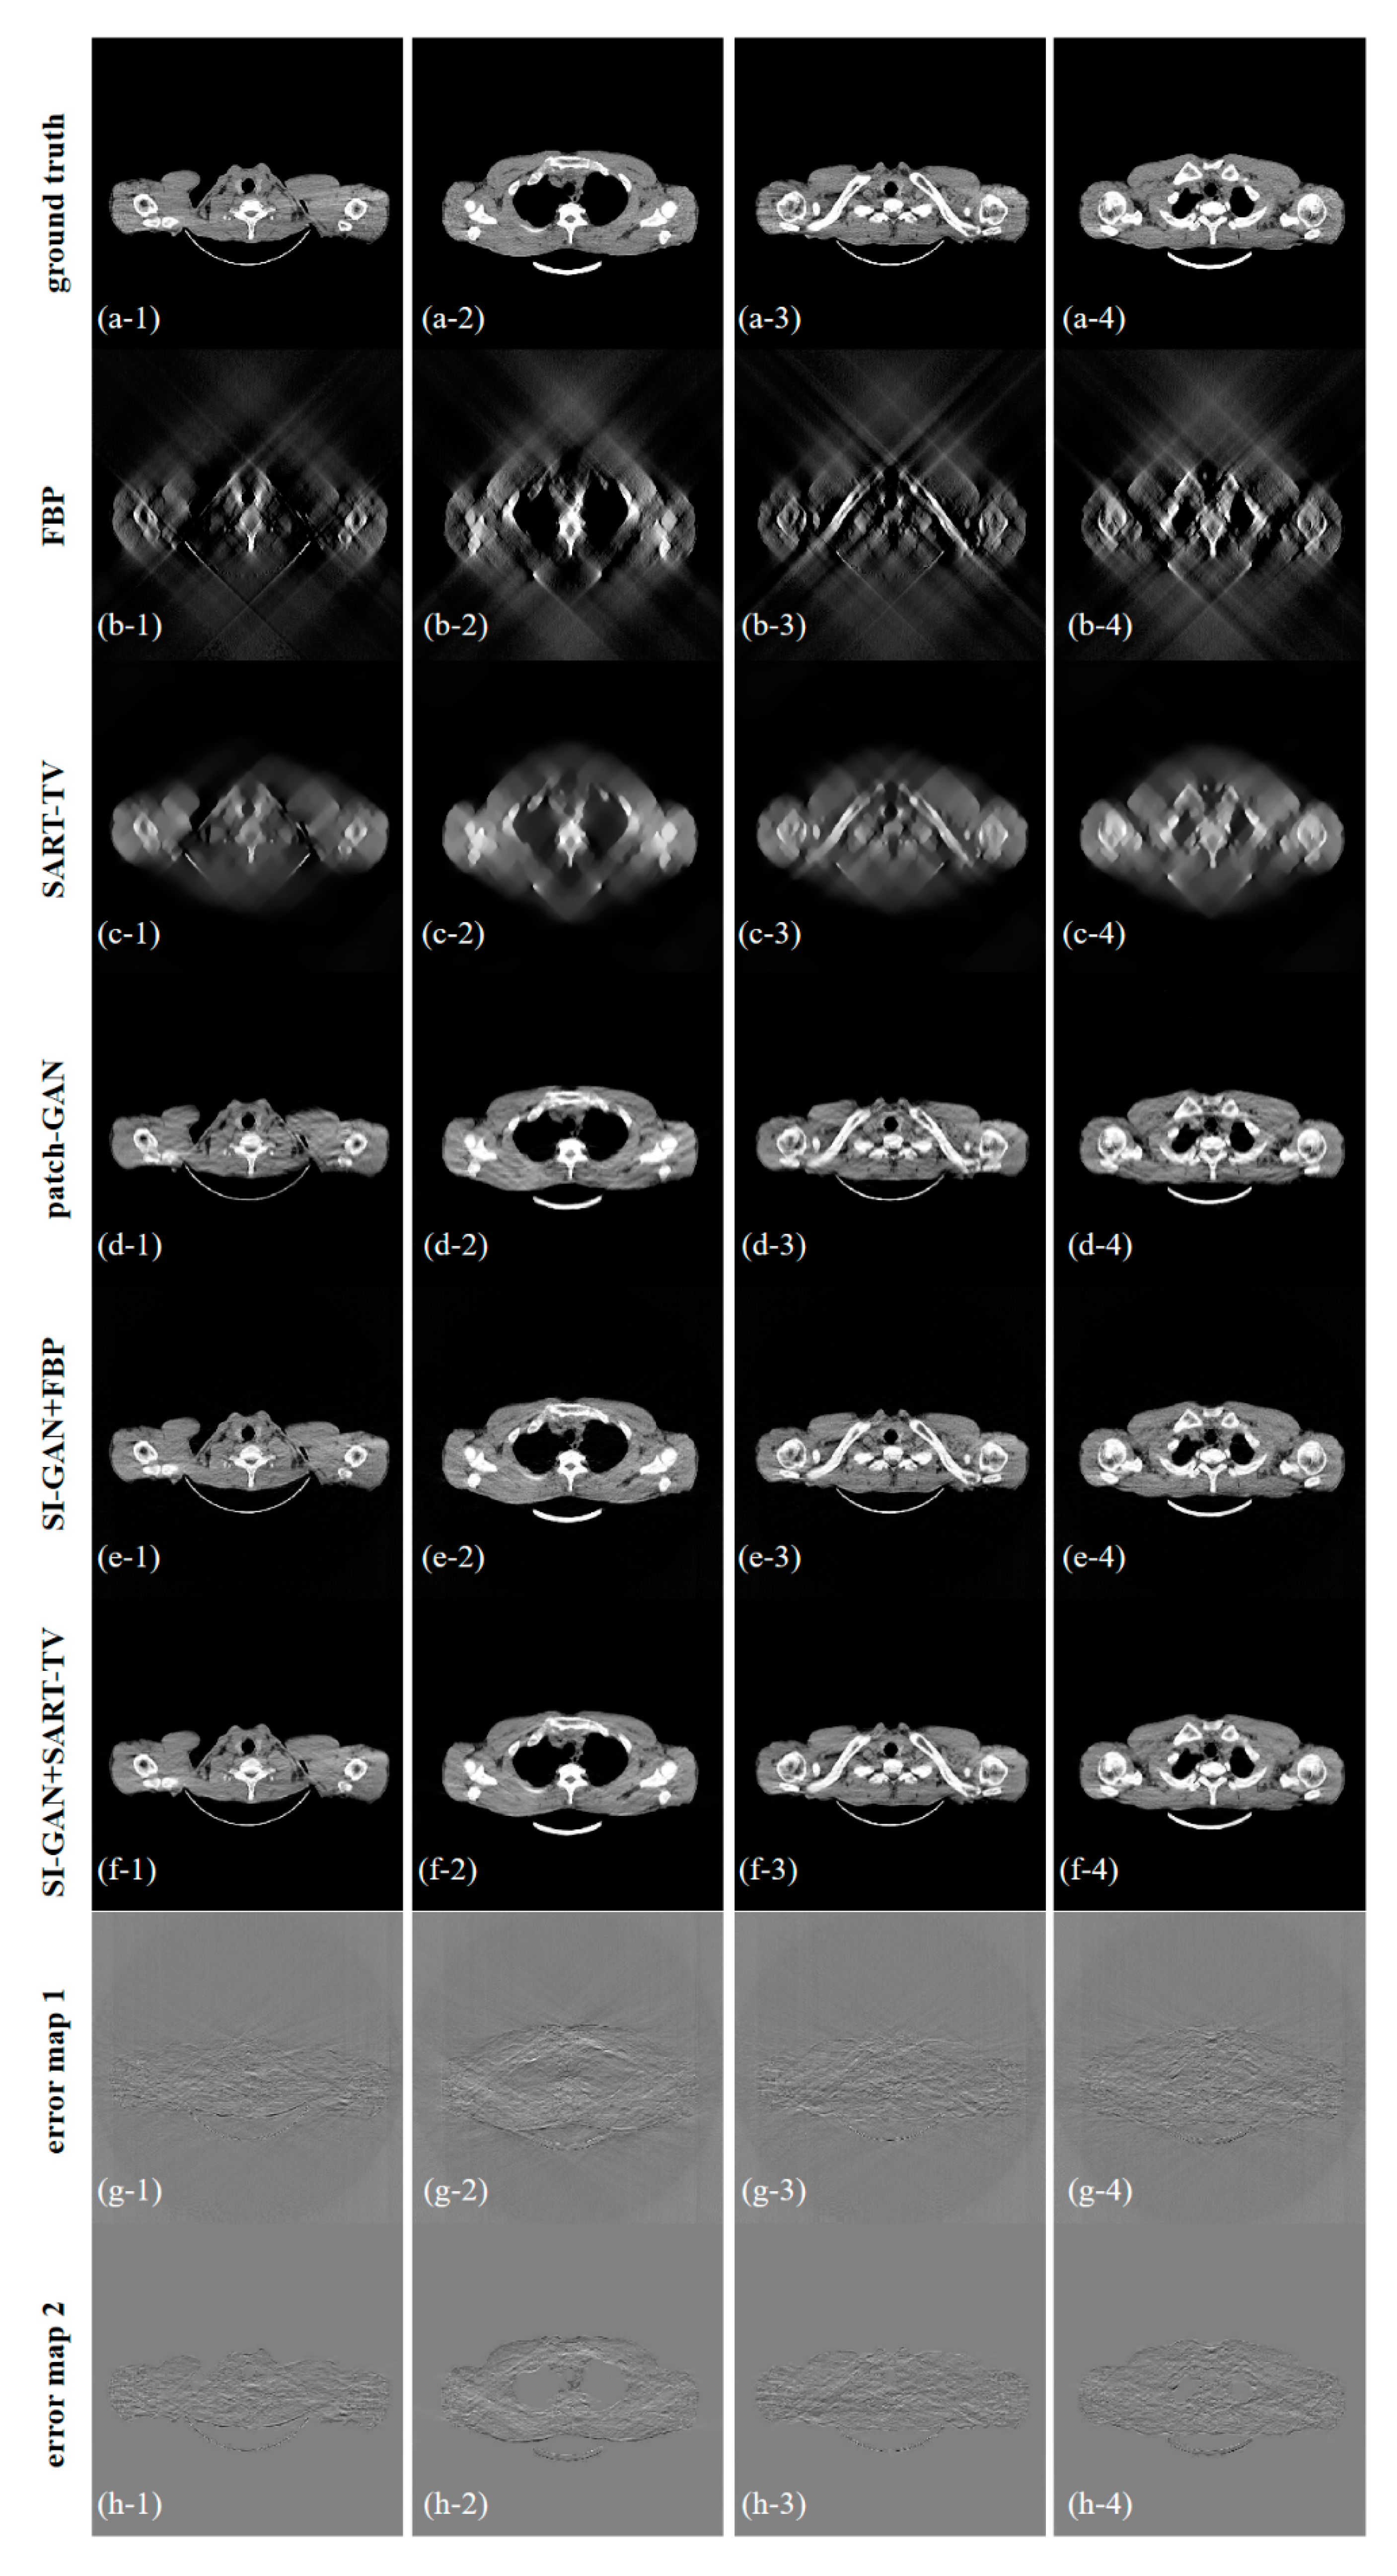

| avg. PSNR | avg. RMSE | avg. NMAD | avg. SSIM | |

|---|---|---|---|---|

| FBP | 17.234 | 0.0553 | 1.5684 | 0.2631 |

| SART-TV | 18.792 | 0.0317 | 0.6512 | 0.7479 |

| patch-GAN | 28.369 | 0.0131 | 0.1828 | 0.9433 |

| SI-GAN () + FBP | 27.230 | 0.0164 | 0.3493 | 0.8513 |

| SI-GAN () + SART-TV | 28.122 | 0.0139 | 0.1933 | 0.9466 |

| SI-GAN + FBP | 29.209 | 0.0114 | 0.2689 | 0.8657 |

| SI-GAN + SART-TV | 31.052 | 0.0093 | 0.1264 | 0.9648 |